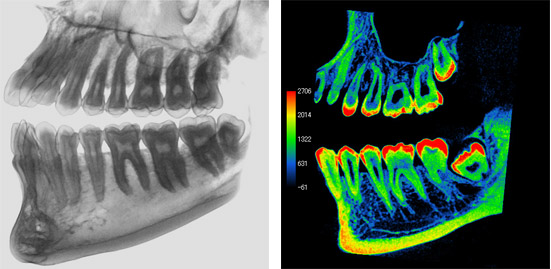

Perio

The combination use of both 3D and multi-slice cone beam CT images provides a sharper understanding of the bony defects within relation to surrounding local anatomy.

In addition to helping the dentist plan for treatment options the patients can also view and become educated on any perio degenerated conditions for better acceptance of ensuing treatments.